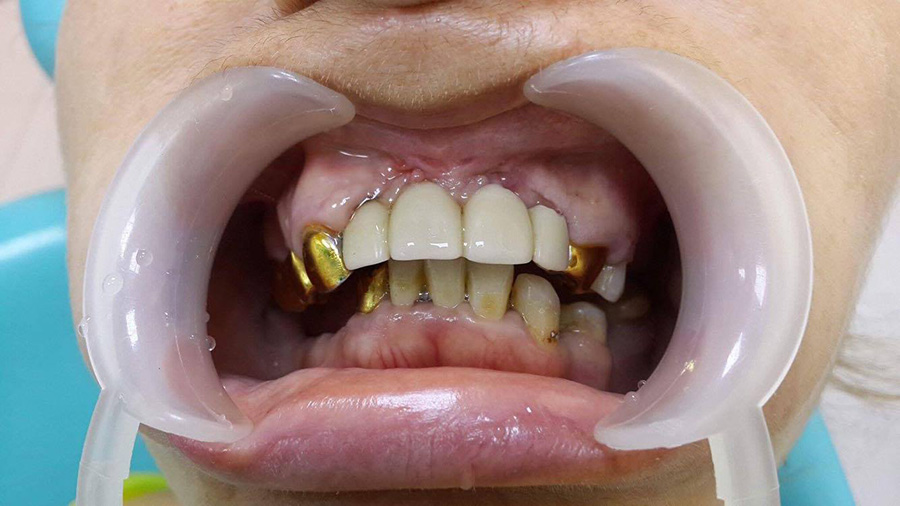

The patient turned to the doctor with the presence of a retinas tooth. The tooth was surgically removed.